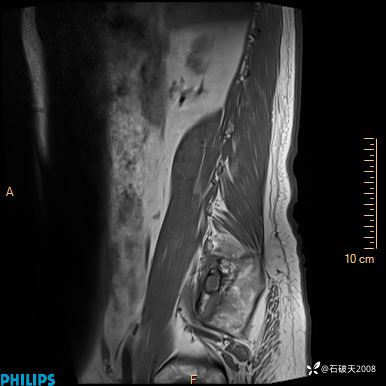

2023年3月份MRI影像

T1矢状位